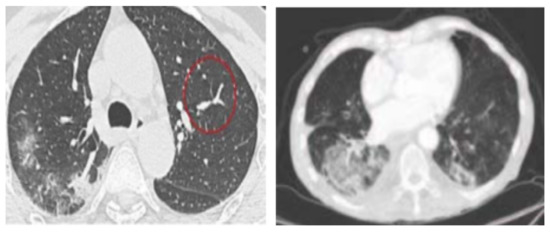

4.1. Feature Extraction Step

4.2. Data Sets